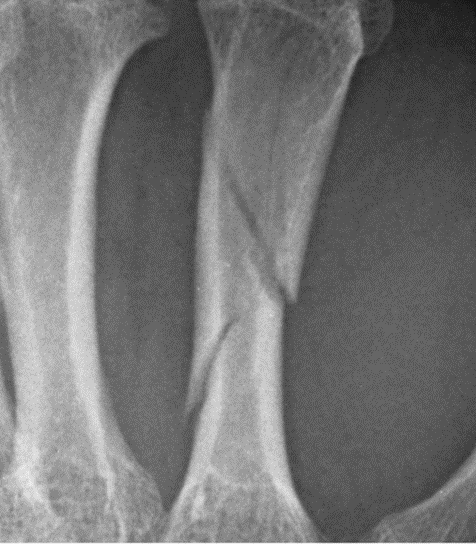

What type of fracture is this?

Spiral

Due to rotation causing fracture